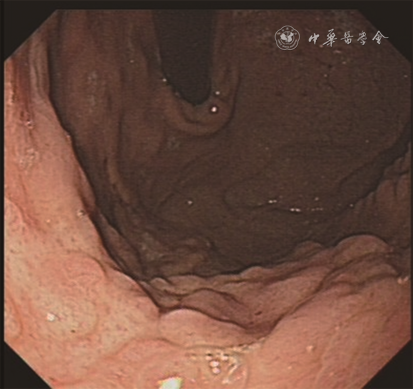

入院查体:神志清,面色苍白,下腹轻压痛,无反跳痛。辅助检查:铁代谢示血清铁降低(3.3 μmol/L),铁蛋白降低(3.0 μg/L),不饱和铁结合力升高(80.3 μmol/L),总铁结合力升高(83.6 μmol/L),转铁蛋白饱和度降低(4%)。钙卫蛋白升高(361 μg/g)。超敏C反应蛋白、叶酸、维生素B12、抗核抗体、抗中性粒细胞胞质抗体、免疫球蛋白及补体均无殊。胃镜示胃体黏膜弥漫性结节样隆起(图2),胃窦及十二指肠黏膜无殊。RUT阴性。胶囊内镜及结肠镜无殊。组织病理学示胃体黏膜呈中度慢性炎,部分上皮脱落,隐窝上皮内淋巴细胞增多(>25个/100个表面上皮),淋巴细胞无异型。上皮下见斑片状胶原沉积(图1D),最厚处68 μm。胃体嗜酸粒细胞计数约18个/高倍镜视野。胃窦、小肠及结直肠黏膜无异常。Masson三色及天狼猩红染色见不规则胶原沉积;美兰、刚果红染色阴性。诊断为CG。

CG内镜检查典型表现为黏膜呈萎缩性或结节性改变。其他表现包括黏膜红斑、溃疡、侵蚀、息肉样病变和增生性红色皱褶[3]。本组4例患儿内镜下表现与文献报道相似。CG的诊断标准是组织病理学可见黏膜呈慢性炎改变,包括固有层淋巴浆细胞、嗜酸粒细胞增多,表面上皮内淋巴细胞增多,上皮损伤和脱落以及腺体萎缩、幽门腺化生[4]。上皮下胶原沉积厚度常超过10 μm,内可见扩张的毛细血管,上皮下增厚的胶原带以Ⅲ型和Ⅵ型胶原为主,胶原可用Masson三色和天狼猩红特殊染色显示。Arnason等[5]根据炎症细胞浸润模式将CG分为3型:淋巴细胞性胃炎型、嗜酸细胞增多型和萎缩型;淋巴细胞性胃炎型可能与乳糜泻相关。本组例3为淋巴细胞性胃炎型,此例患儿曾有腹泻病史,但未累及十二指肠及结直肠黏膜,余3例患儿为嗜酸细胞增多型。本组例1及例4患儿累及十二指肠黏膜,但临床未曾有腹泻症状,暂未做乳糜泻相关检查,未摄入无谷蛋白饮食,与乳糜泻的关系尚不明确。